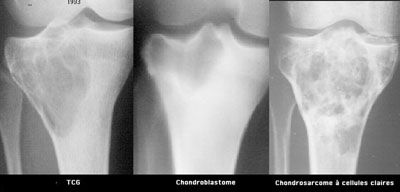

Pédagogie Conduite à tenir devant une tumeur à cellules géantes , Bernard Tomeno Hôpital Cochin, Paris, France N°136 - Août 2004 ● 16 min de lecture